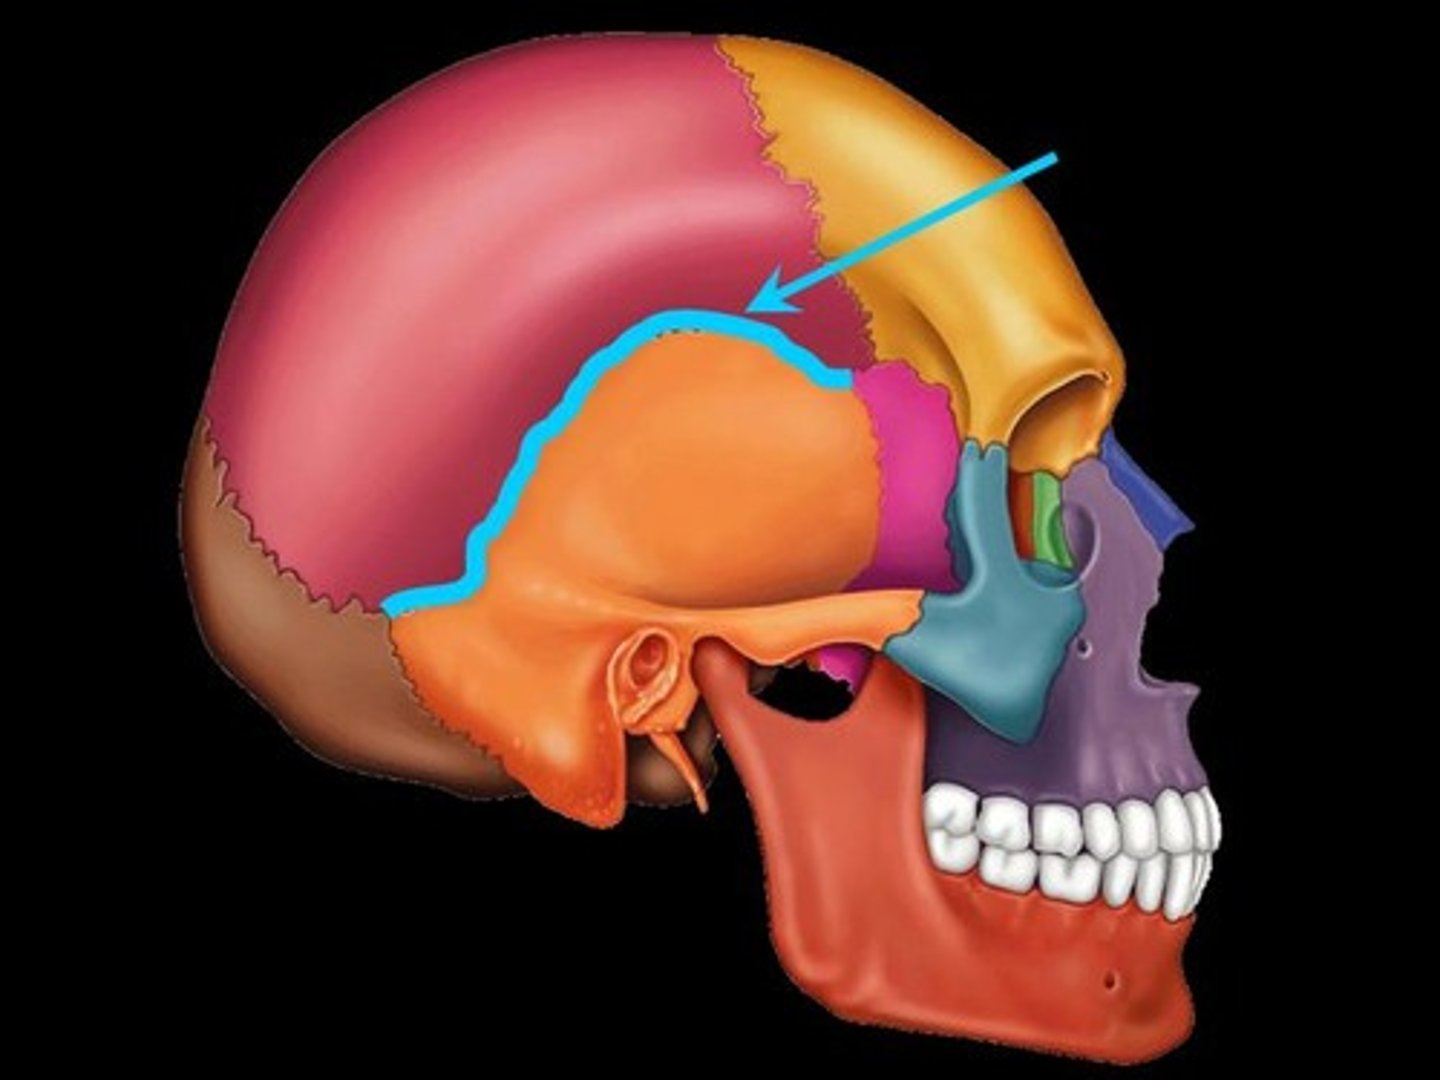

4 Main Sutures of the Skull

- Squamous

Squamous Suture

Suture between parietal and temporal bones